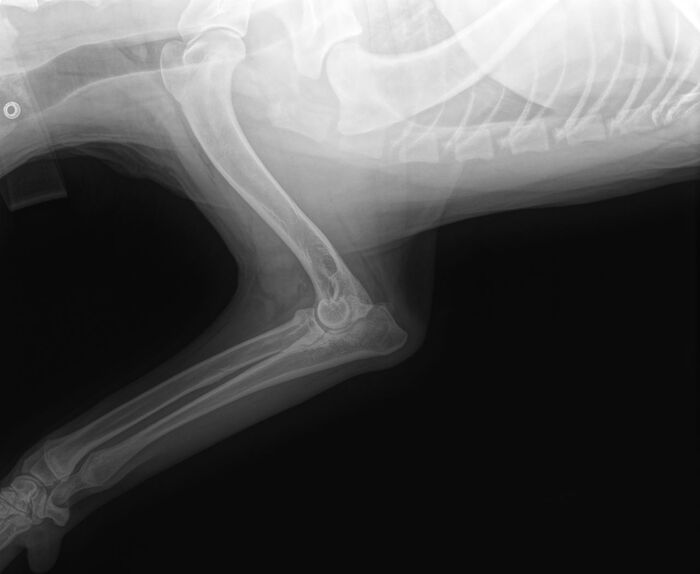

Операция на локтевом суставе у щенка немецкой овчарки

Диспозиция такая, щенок немецкой овчарки 8 мес. начал прихрамывать на переднюю правую лапу. Обратились в клинику, поставили предварительный диагноз "дисплазия правого локтевого сустава, фрагментация медиального венечного отростка", отправили на КТ, которое подтвердило диагноз "фрагментация медиального венечного отростка справа. Дисконгруэнтность суставных поверхностей (эффект ступеньки) правого локтевого сустава. Дисплазия правого локтевого сустава.".

Врач рекомендует операцию по удалению отломков, и предлагает сразу сделать остеотомию, удалить часть кости чтобы устранить "ступеньку". Если по удалению отломков вопросов нет, делать надо, т.к. они причиняют боль и вызывают воспаление. То вот по поводу остеотомии есть сомнения, обчитавшись статей в интернете заработал себе раздвоение мнений, с одной стороны пишут что после операции стало еще хуже, кто-то пишет что отказались и собака спокойно себе живет и бед не знает. Есть и обратное, сделали операцию и все отлично, и отказались и собака через пару лет стала инвалидом.

С одной стороны можно пока удалить отломки и посмотреть как будет дальше. С другой стороны может стать хуже и тогда вторая операция, еще раз вскрывать сустав, еще одна седация, еще один стресс для собаки и хозяев...

В общем вдруг кто-то сталкивался, или разбирается в этой теме... реально не знаю что делать, хочется как лучше...

Операция назначена на 4 Апреля, будем удалять отломки. Делать ли сразу остеотомию пока думаем.

Для "шарящих" прикрепляю картинки из клиник и видос как хромает.